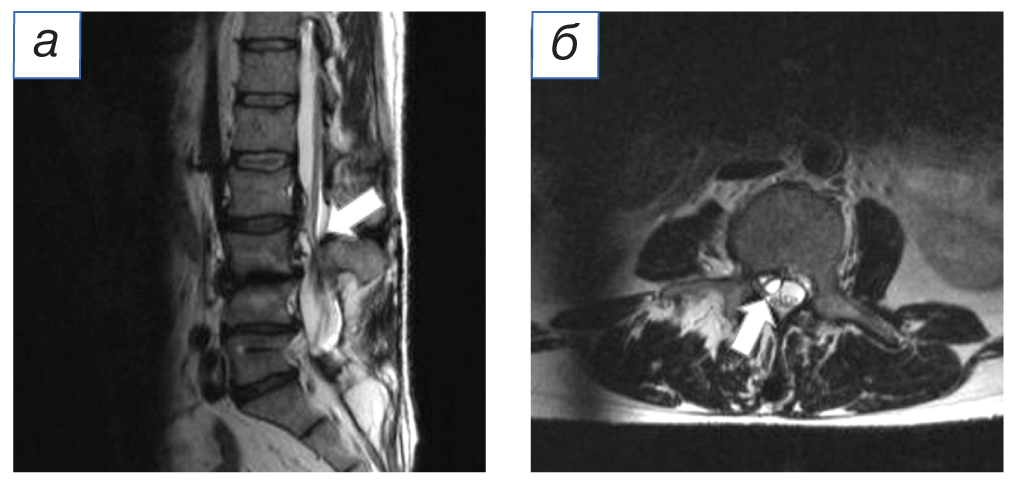

Через 5 лет после операции возобновились боли в области поясницы, правой и левой нижних конечностях, возникла слабость в левой стопе. При контрольном обследовании (рентгенография, мультиспиральная компьютерная томография и магнитно-резонансная томография) поясничного отдела позвоночника выявлены перелом правого верхнего винта системы транспедикулярной фиксации, стенозирование позвоночного канала на уровне LIII–LIV (рис. 1–3).

Рис. 3. Мультиспиральная компьютерная томография: а (аксиальный срез) — стрелкой показана область перелома транспедикулярного винта; б (сагиттальная реконструкция) — стрелкой отмечена область дегенерации над стабилизированным позвоночно-двигательным сегментом.

Fig. 3. Multispiral computed tomography: а (axial section) — the area of the pedicle screw fracture is highlighted. б (sagittal reconstruction) — marked area of degeneration over the stabilized spinal motion segment.

По результатам мультиспиральной компьютерной томографии: дегенеративно-дистрофические изменения поясничного отдела позвоночника; левосторонний поясничный сколиоз; состояние после оперативного вмешательства, наличие металлоконструкции на уровне LIV–LV, перелом правого верхнего винта.